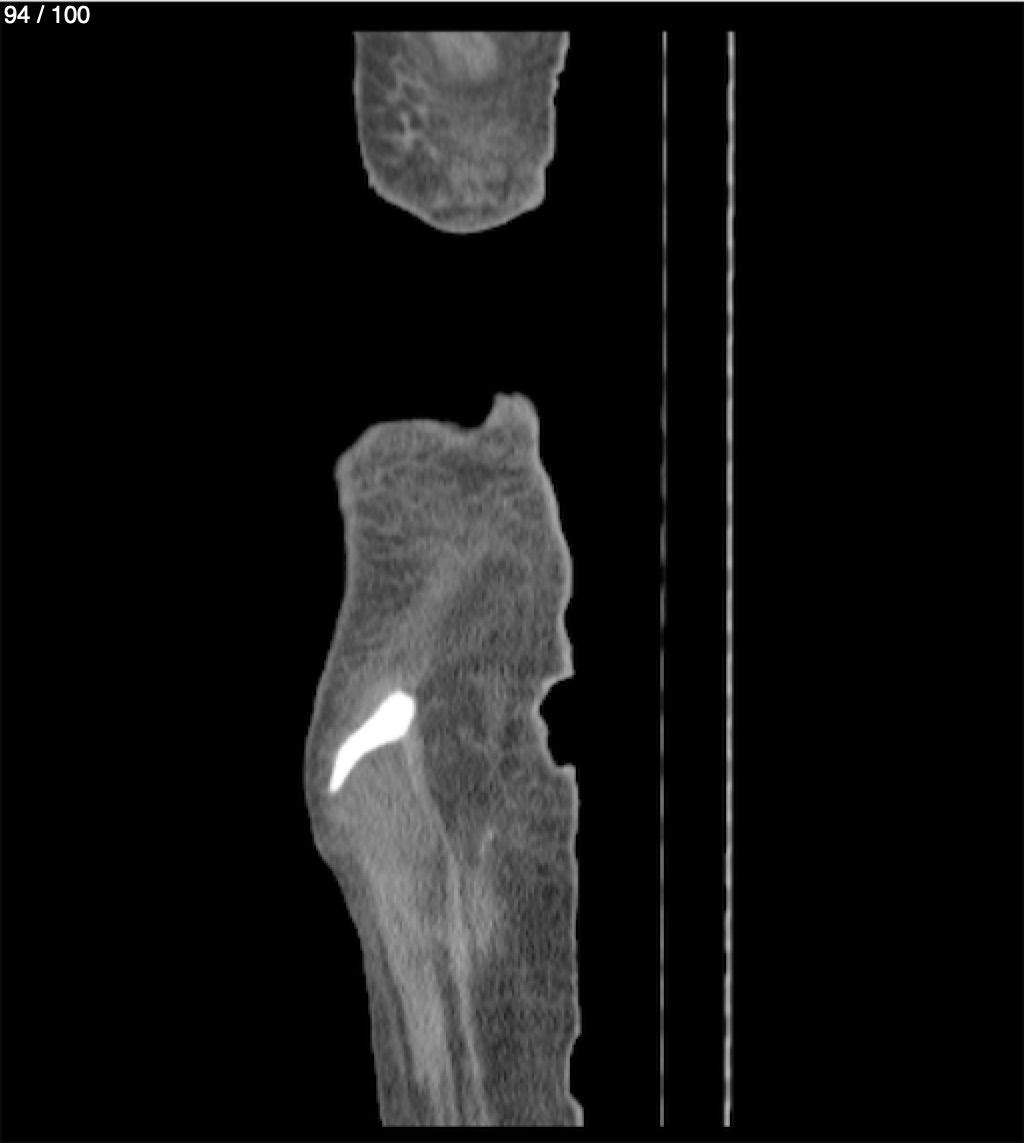

Hilda Geronimo Mendez 60A - T.C Abdomen Simple